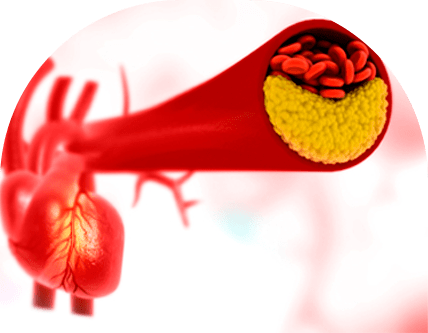

Favorece o acúmulo de placas nos vasos sanguíneos

Com o tempo, o excesso de LDL pode se depositar nas paredes das artérias. Esse processo, chamado de aterosclerose, dificulta a passagem do sangue e pode causar obstruções. É uma construção lenta, que pode começar na juventude e se agravar com os anos.

Aumenta o risco de infarto, AVC e doenças cardiovasculares

Quando as artérias do coração ou do cérebro são afetadas por essas placas, o risco de infarto e AVC aumenta. Muitas vezes, esses eventos são a primeira manifestação do problema, por isso, o acompanhamento preventivo é tão importante, mesmo sem sintomas.